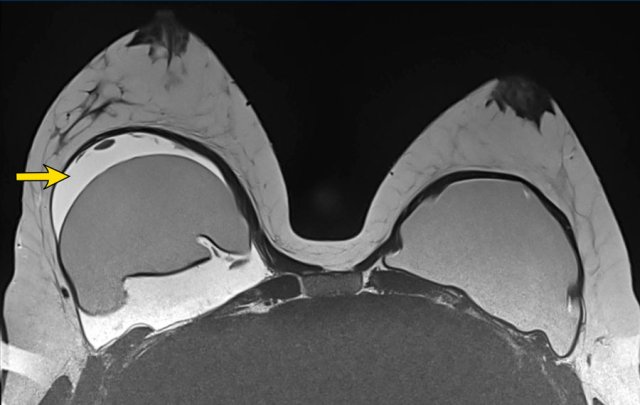

Intracapsular rupture

When there is silicone within a fold, then it is a sign of intracapsular rupture.

The images show:

- Teardrop sign: where the walls touch each other (1).

- Keyhole or Noose sign: different shapes, the walls do not touch each other (2-3).

Here another example of the different presentations of intracapsular rupture with silicone outside the envelope, but within the capsule.

- subcapsular line (yellow arrow)

- nose sign (blue arrow)

- teardrop sign (red arrow)

Linguine sign

This is the most reliable sign of intracapsular rupture.

The curvilinear lines which are formed by the ruptured envelope resemble Linguine pasta.